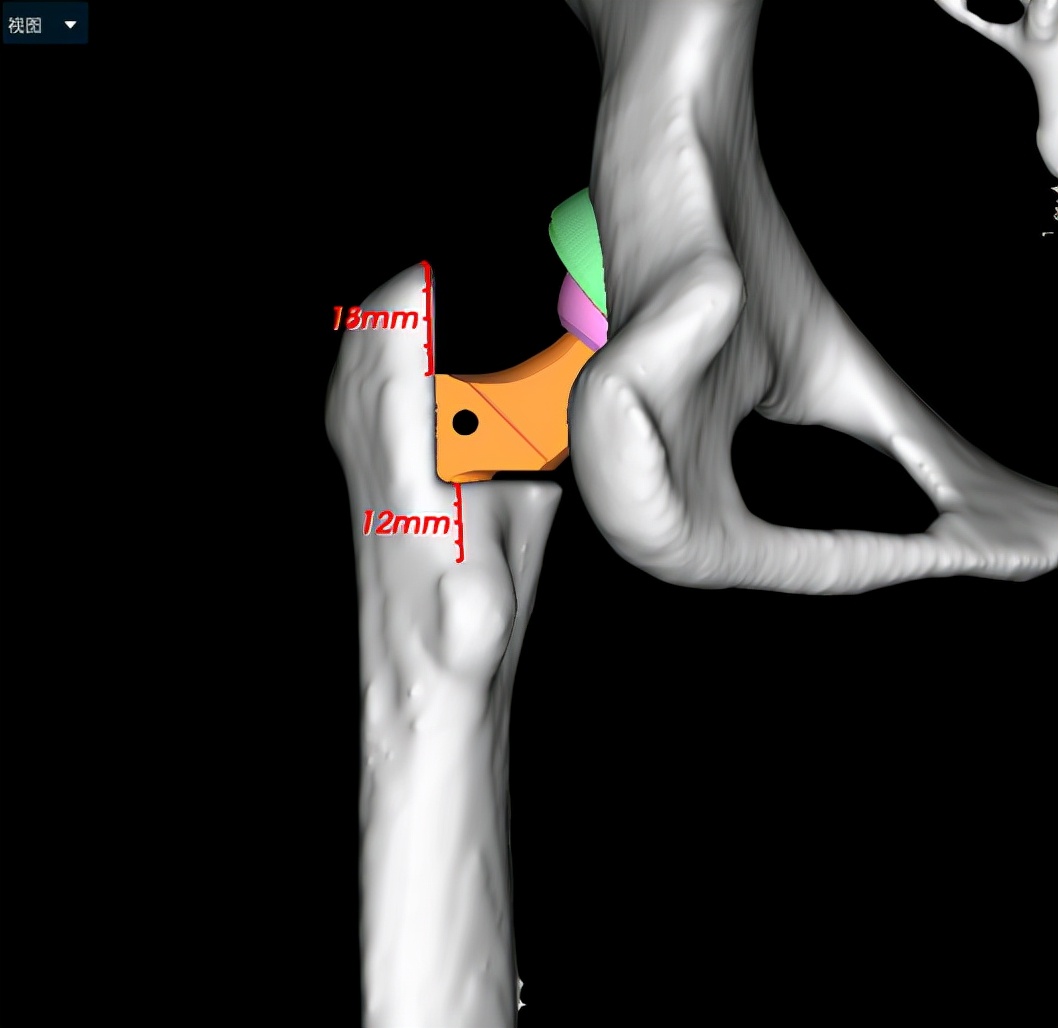

小张入院后,立即开始逐步进行相关检查,进行术前的准备。因为DDH的手术一般比较复杂,特别是这种脱位程度较高的患者,所以术前就需要更加精准的规划。对于小张的手术方法,耿硕副教授制定了两套方案:1.如果原来真臼内及股骨头的软骨条件良好并且相匹配的话,那么可以尝试将股骨头放进髋臼里配合骨盆截骨重建髋关节;2.如果软骨条件不好或难以匹配,那么只能行全髋关节置换术。但是所有手术方案都会有一个挑战,就是如果在安装完髋臼杯及股骨假体后复位时把股骨下拉过多,可能会造成神经等软组织的牵拉伤并且且因软组织张力过大可能造成假体松动,为了避免这种情况可能需要行股骨截骨减张,这样一期便不能恢复双下肢等长,需二期行骨延长术恢复下肢等长。在术前,为了适应软组织的张力状态及验证复位可能性,小张入院后即进行了患肢的牵引处置。为了精准的对手术做出规划,术前小张进行了下肢全长的三维CT扫描和模型重建,并且应用人工智能系统AI HIP对其进行术前手术方案的制定。人工智能能够利用患者的三维CT数据进行智能化识别解剖位点,匹配假体的大小及安放位置,通过对手术精准地预演,让外科医生在术前心中有数。通过人工智能系统的规划,计算出小张同学的双下肢腿长差和偏距差,计算出了旋转中心所需下移的距离和假体需要安放的位置等,髋关节置换方案为S-ROM假体系统,髋臼杯为PINNACLE 44号,内衬为BIOLOX28-44,因为患者比较年轻,所以选用了陶瓷对陶瓷的摩擦界面,能够实现更长的使用年限。根据术前规划数据,毕郑刚、耿硕团队提前准备了相应的假体和器械,为手术做了充分的准备。

人工智能术前规划